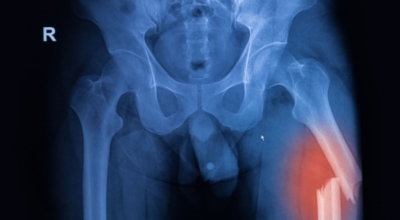

글루코사민에 대조해 원료가 100배가량 비싼 고가의 원료인것으로 알려져 있습니다. 관절염 이유가 되는 것으로는 관절 연골이 닳아 없어지기 때문인데 퇴행성 질환이라고 부르는 이유가 연골이 더 이상 생성되기 어렵기 때문이죠. 특히 콘드로이친이라는 성분이 나이가 들면서 길이가 짧아지고, 크기가 줄어들기 때문에 연골 구조가 변화되어 가면서 무릎뼈의 간격이 좁아져 통증을 유발하는 원인인데 이때 콘드로이친 효능을 바라볼 수 있어요.

나이가 점점 들수록 보행 속도가 자연적으로 느려지게 되는데, 그 이유는 바로 관절의 노화 때문입니다. 노화가 진행되면 연골 손실이나 관절 간격이 짧아짐에 따라 관절염이 발생하고, 그로 인해 통증이 생겨 보행력이 점점 저하가 될 수 밖에 없다고 합니다. 이 때문에 나이가 들수록 콘드로이친을 보충시켜 주는 것이 보행역량 개선에 도움을 줄 수 있는 방법중 하나 입니다.

콘드로이친은 대부분이 골관절염 증상 관리를 위한 치료제로 쓰이고 있습니다. 미국에서 시행된 골관절염 환자 604명을 대상으로 한 연구에서 콘드로이틴의 골관절염 통증 관리의 효과를 관찰했는데 그 결과, 콘드로이틴이 무릎 골관절염 통증이 있는 사람들의 약 10%가 통증완화와 개선효과를 체험하였습니다. 그 이유는, 노화가 진행되는 중장년층에게서 콘드로이친 수치가 저하되는걸 볼 수 있습니다.

이는 곧 연골의 뼈와 뼈 사이 완충효과 및 보호기능 약화로 이어지는데 이를 보충하면 관절염을 해결하는데 도움 됩니다. 그리고 콘드로이친은 관절세포를 재생시키는데 도움이 되고 외부 충격을 흡수, 완화하는데에도 가장 좋은 효과가 있습니다.

콘드로이친에는 관절 통증 감소 효험도 있습니다. 콘드로이친은 보통 관절염으로 인한 무릎 통증을 관리하기 위해 사람들이 많이 필요로 하는 성분입니다. 관절염의 증상을 덜어줄 수는 있지만 섭취로 인한 효과가 영구적으로 지속되지는 않습니다. 그렇기 때문에 별개의 관절염 치료와 복용을 병행하시는 것이 더 좋아요.

콘드로이친 중 가장 대표적인 것이 연골세포를 보존하는 역할이라고 합니다. 콘드로이친에는 연골세포의 분해를 억제시켜 연골세포를 보호해주며 유지시켜주는 기능이 있습니다. 연골은 노화가 진행될수록, 나이가 들 수록 점점 그 크기가 감소하거나 끊어질 수 있지만 이때 콘드로이친이 그 스펀지와 같은 역할을 하여 연골 속 수분을 잡아주어 부드럽고 유연하게 유지할 수 있도록 도와준다고 알려져 있답니다.

하지만 콘드로이친은 신체 내에서 자연적으로 생성을 할 수 없어 외부에서 추가적으로 보충되어줘야 하는데 나이가 들면서 점점 콘드로이친이 부족하게 되면 무릎이나 손목의 통증, 관절염 등 자연 노화로 인해 피할 수 없이 오는 질환들이 발생할 수 있다고 해요. 그뿐 아니라 아침에 일어났을 때 주로 일어나는 관절 경직 증상 완화에도 큰 도움 됩니다.

관절염으로 인한 통증은 환자의 몸의 기능을 쇠약하게 만들기도 합니다. 좀 더 유심히 말하자면, 관절염으로 기인해서 몸을 움직이지 않아 일상 활동과 삶의 질에 영향을 미치게 됩니다. 한 프랑스에서 모두 만들어진 연구에 의하면 12개월간 관절염 환자에게 하루에 800mg의 콘드로이친을 전달한 결과 위약을 복용시킨 대조군에 대조해 기능 역량이 50% 내외로 향상된 결과가 나왔습니다.

또 다른 연구를 보면 콘드로이친 복용이 무릎 관절의 마찰 계수를 낮추는 것으로 보여 집니다. 즉, 연골이 보다 부드럽게 움직일 수 있도록 도와 관절 기능에 도움이 되는 것 이예요.